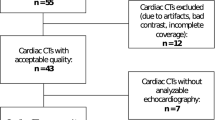

A total of 237 patients with basic clinical information and coronary CTA examination data were enrolled. 546 patients were excluded from the study population (arrhythmias (n = 43), valvular heart disease (n = 45), cardiomyopathy (n = 54), congenital heart disease (n = 21), poor image quality (n = 35), a history of coronary artery reconstruction (n = 176), or insufficient clinical data (n = 172)). The general clinical characteristics and cardiac function parameters of each group are detailed in Table 1. The differences in age, sex, body mass index (BMI), CACs, LVEF, and LVESV were significantly different between groups.